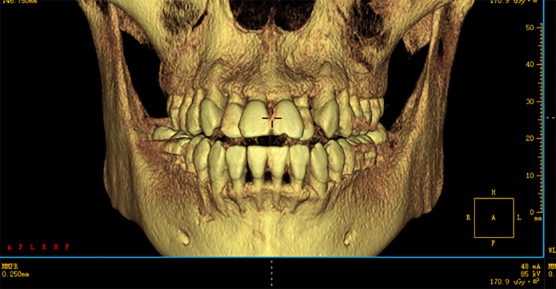

4.Influence of CBCT in the field of oral treatment

Application of CBCT in invisible orthodontic treatment

1.The role of CBCT in orthodontics

2.Diagnosis of embedded teeth

3.Measurement of bone mass and implantation site of implant anchorage

4.Detection of root resorption and joint reconstruction in the process of orthodontic treatment

5.Study on the morphological characteristics of airway